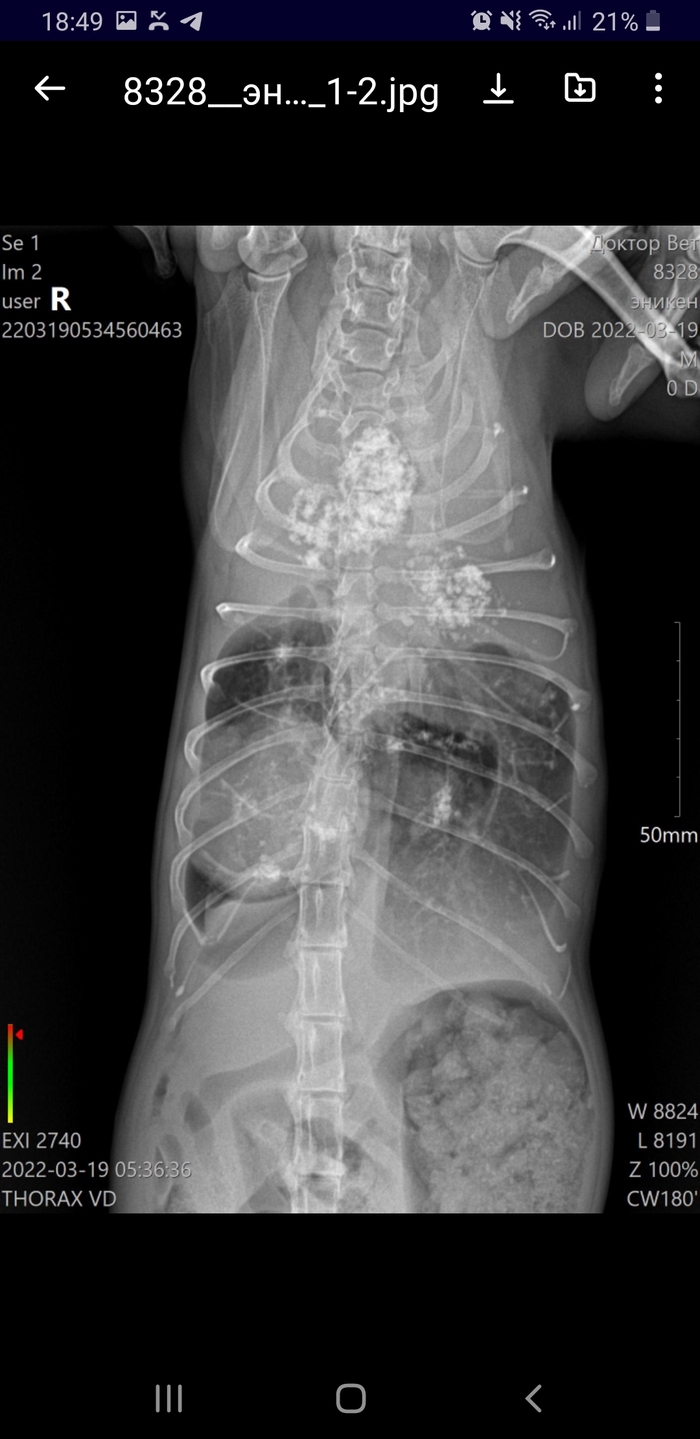

Здравствуйте! Энакину ставили кальциноз бронхов,прошёл назначенный курс лечения.Да,каюсь,после лечения не прошли повторный рентген, умирала наша другая кошка-Туся,очень долго и тяжело, немного задвинули его на второй план.Ждали когда потеплеет, чтобы везти на осмотр и приём,т.к. в Якутске не хочется лишний раз таскать лысого кота по улице,хоть и занимает несколько десятков секунд,но все равно боялись(может и оправдывали свое бездействие-не спорю)

Это рентген за сеоодняшний день,здесь уже чётко видно новообразование, у кота начались приступы,задыхается.